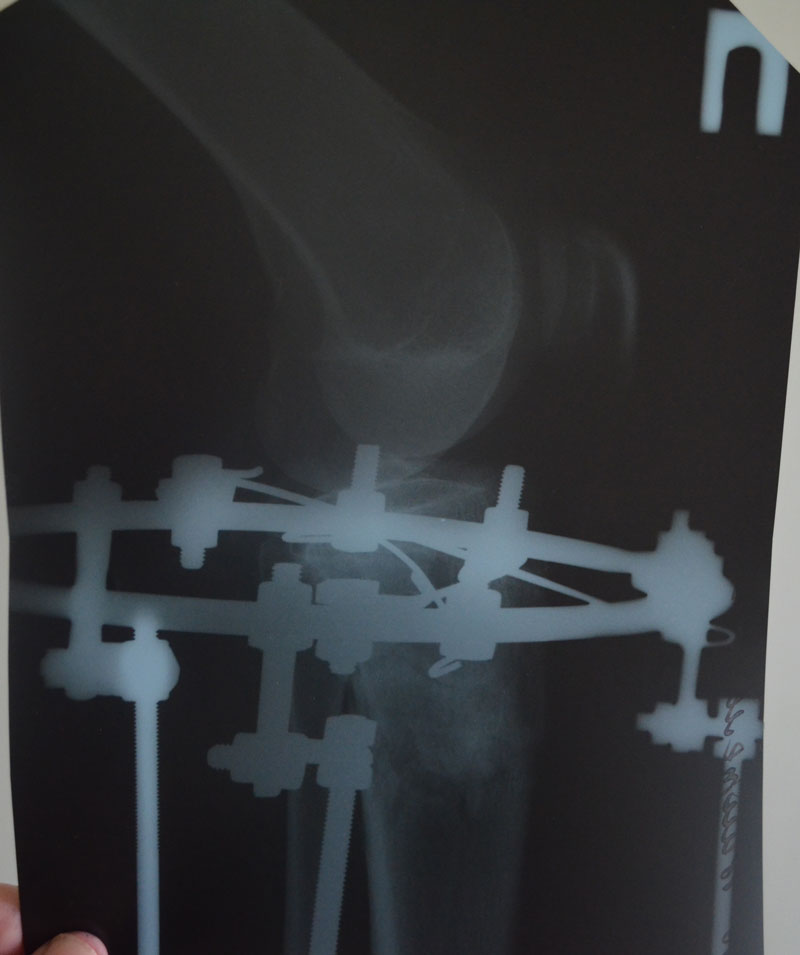

Всё хорошо, ножки ровные, продолжаем фиксацию!

По рентгену, ось ровнейшая. Правая срослась, а левая... Ходить Вам ещё минимум 3 недели, после делайте ещё рентген и отправляйте по эл. почте. Начинайте принимать препараты кальция и мумиё - его нужно принимать так: развести в 0,5 л. банке 10 таблеток - мумиё, до полного растворения таблеток. После этого, принимать по 1 ст. ложки раствора 3 раза в день. Хранить в холодильнике.